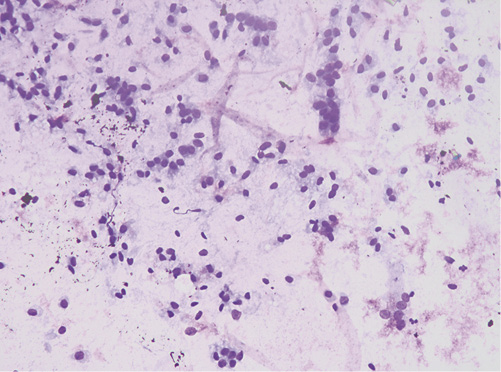

A presumptive diagnosis of disconnected MPD with a gastric fistula due to previous cystic drainage was made, but endoscopic ultrasound (EUS) was performed to exclude a main-duct intraductal papillary mucinous neoplasm (MD-IPMN). Endoscopically, a fistulous orifice 10 mm wide in the gastric antrum was apparent (Fig. 1), with a gelatinous, high-viscosity content which could not be removed despite vigorous lavage. A gastroscope was used to intubate the fistulous tract, but progression was not possible due to the viscous content. The EUS showed a globally dilated MPD (40 mm in the body) with a loss of interface with the gastric wall in the isthmus, 10 mm in diameter (Fig. 2). Fine-needle aspiration (FNA) of the MPD with a 19-gauge needle was performed, revealing a very thick mucinous content. Cytologic analysis confirmed high-grade IPMN, and the patient was referred to surgery (Fig. 3).